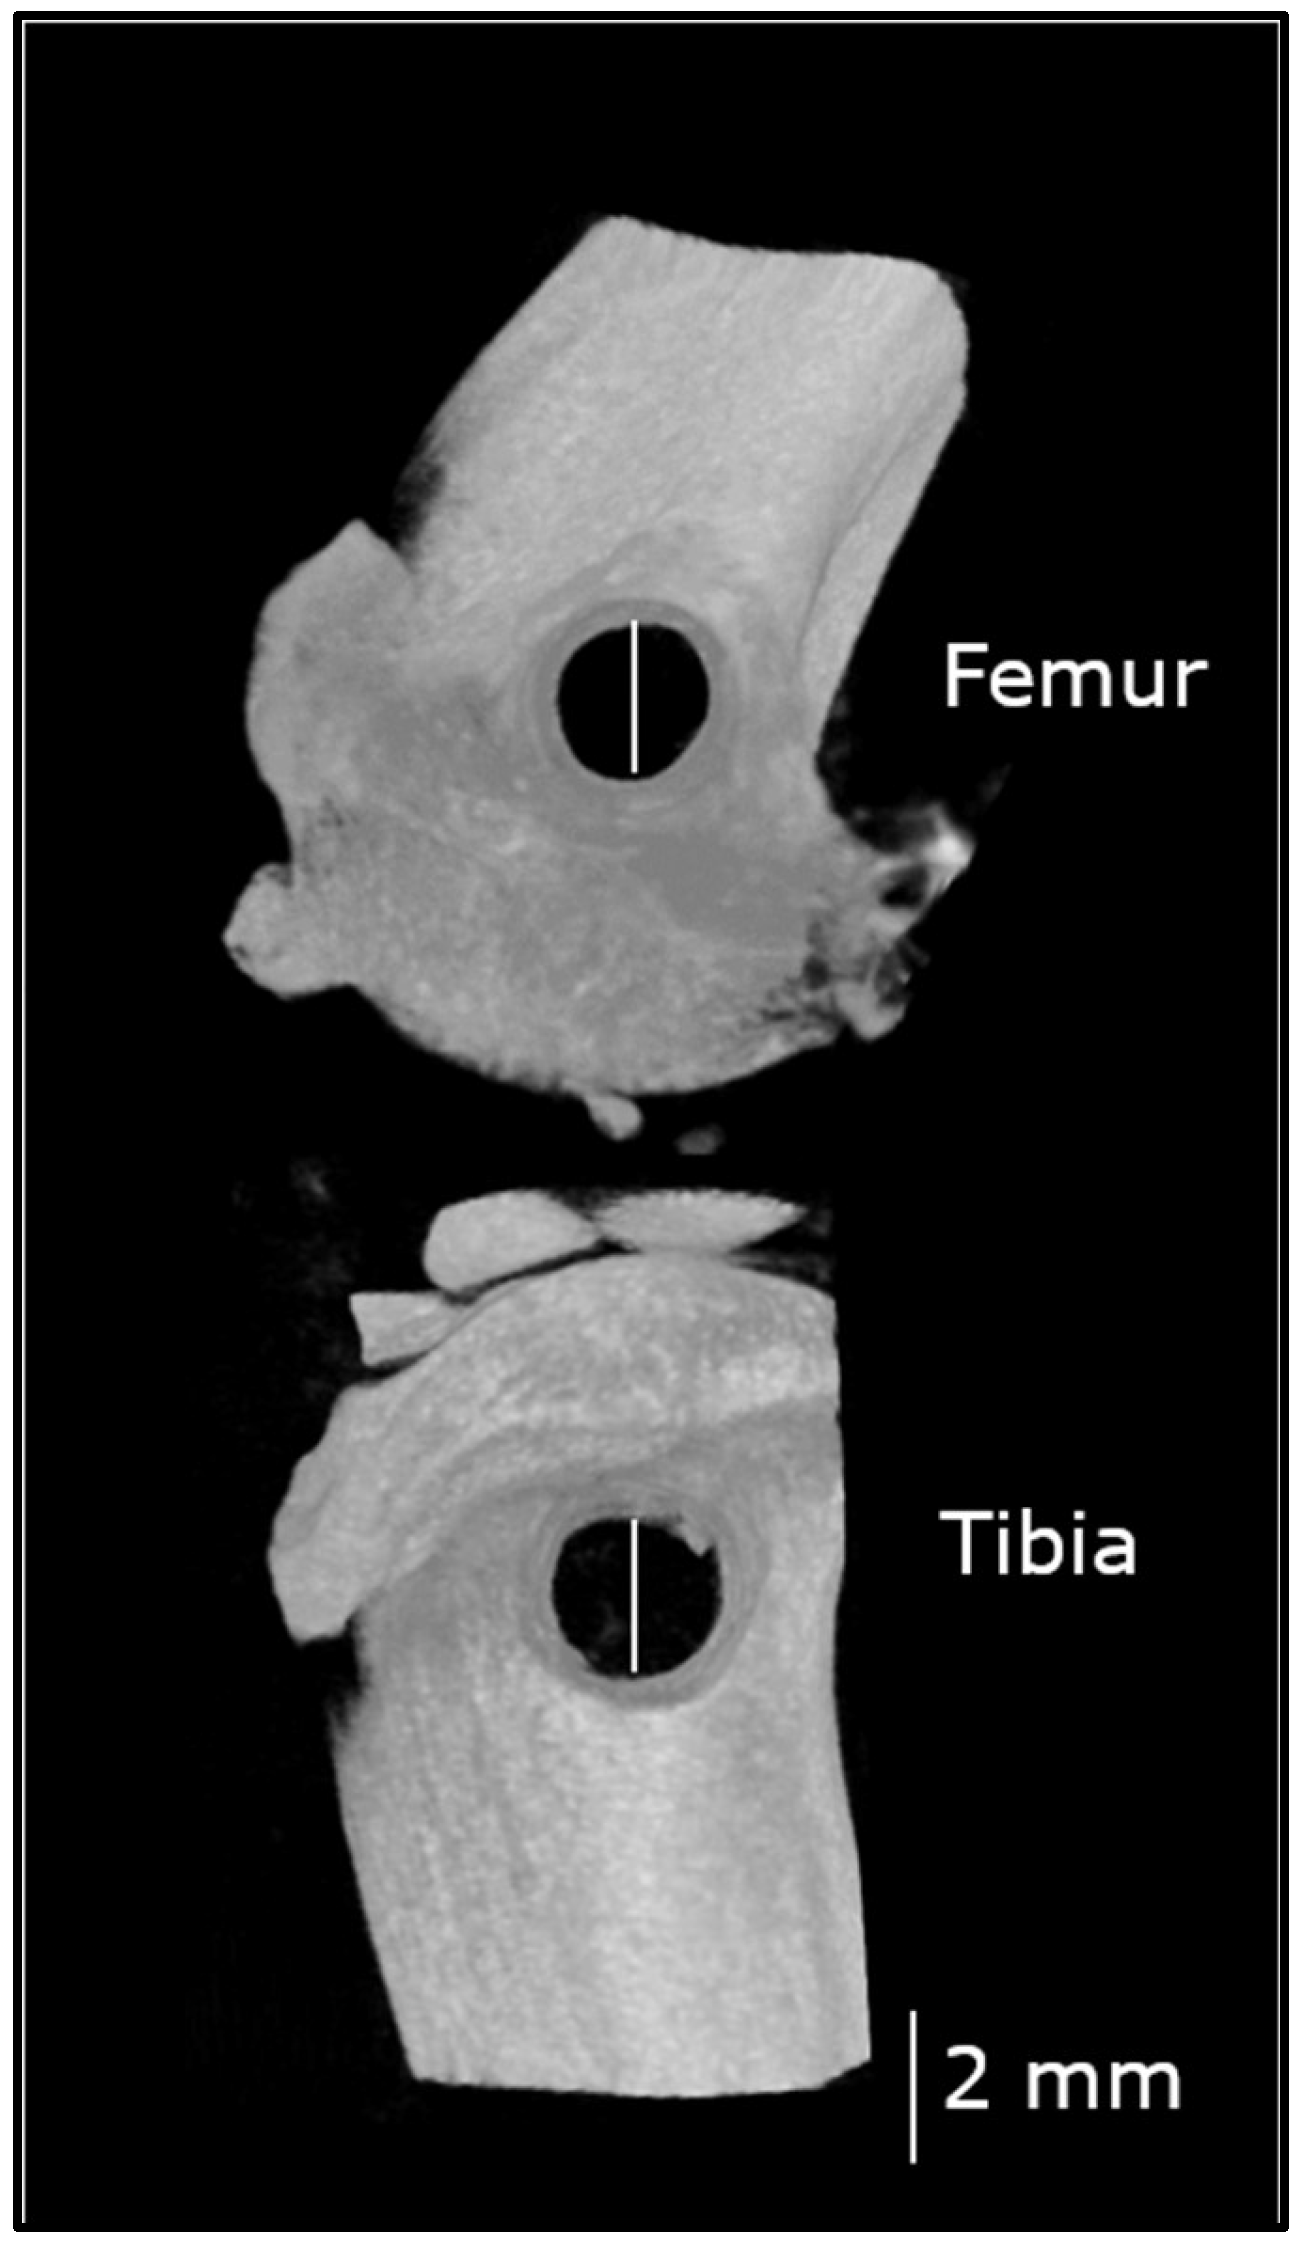

2.6. Postoperative Microcomputed Tomography (µCT) and Computation

2.6.1. µCT Settings

2.6.2. µCT Reconstruction and Data Computation